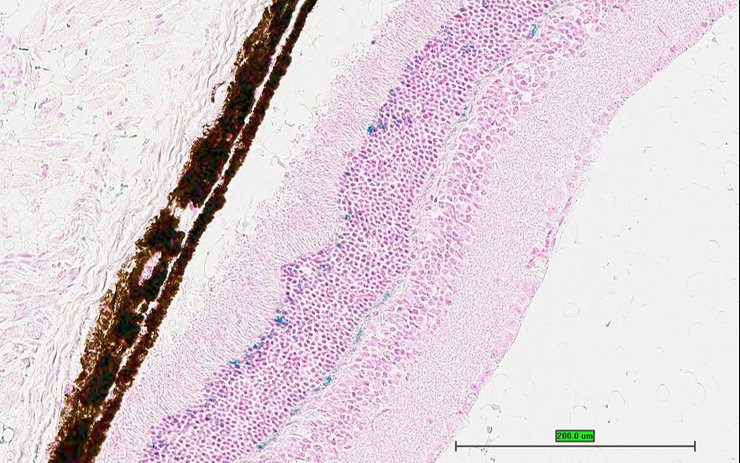

TS28: eye Present UC Davis_1879394

Specimen UC Davis_1879397: postnatal adult; Cnga3tm1.1(KOMP)Vlcg/Cnga3+ (more )